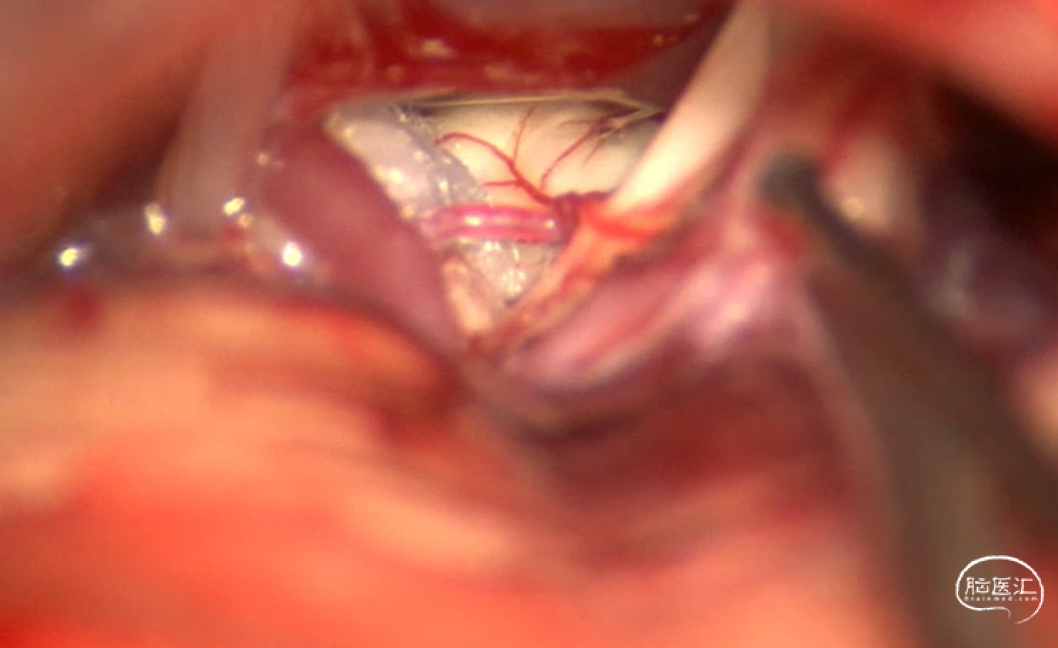

手术过程:常规侧卧位,乙状窦后发迹内直切口约6cm,星点前下方钻孔后铣刀游离骨瓣,磨钻扩大骨窗达乙状窦后缘,剪开硬脑膜后脑组织饱满释放脑脊液后仍不能显露CPA结构,遂将颅骨进一步磨除显露部分乙状窦,形成扩大乙状窦后入路,同时调整头位和显微镜进一步增加对CPA区的显露,在牵开小脑半球释放桥前池脑脊液后颅压下降脑组织塌陷。从后组颅神经处锐性剪开蛛网膜,暴露REZ区未见明显动脉压迫,只有小脑中脚静脉由桥脑于面听神经之间穿行后进入桥静脉汇入颈静脉孔。向后组颅神经腹侧、桥延沟及内听道处探查无动脉压迫,确认单纯静脉压迫。小块的垫棉小心垫于面神经和静脉之间后电生理提示除眼轮匝肌外其余LSR消失,电生理实时监护下反复调整垫棉位置最终LSR消失。水密缝合硬脑膜,骨瓣复位固定,各层严密缝合。术后患者清醒后面部抽搐未发作,听力正常,无面瘫。

术中多角度探查只见粗大静脉,未见明显责任动脉压迫:

于面神经与静脉间置入垫棉在电生理护航下反复调整垫棉位置最终LSR消失。

静脉血管压迫导致的面肌痉挛在临床工作中少见,文献中多为个案报道,缺乏大宗病例报道,其发病率在0-5.5%,也有静脉联合蛛网膜束带导致的面肌痉挛的报道,静脉压迫的MVD其手术操作较动脉血管难度增加,手术操作要求高,但原则是一样的,达到减压隔绝的目的即可,因静脉血管易出血所以动作要轻柔,避免静脉撕裂,在电生理监测下实时观察LSR的变化是手术核心。在3D-TOF-MRA检查怀疑静脉压迫且LSR阳性的患者可以进行MVD手术治疗。